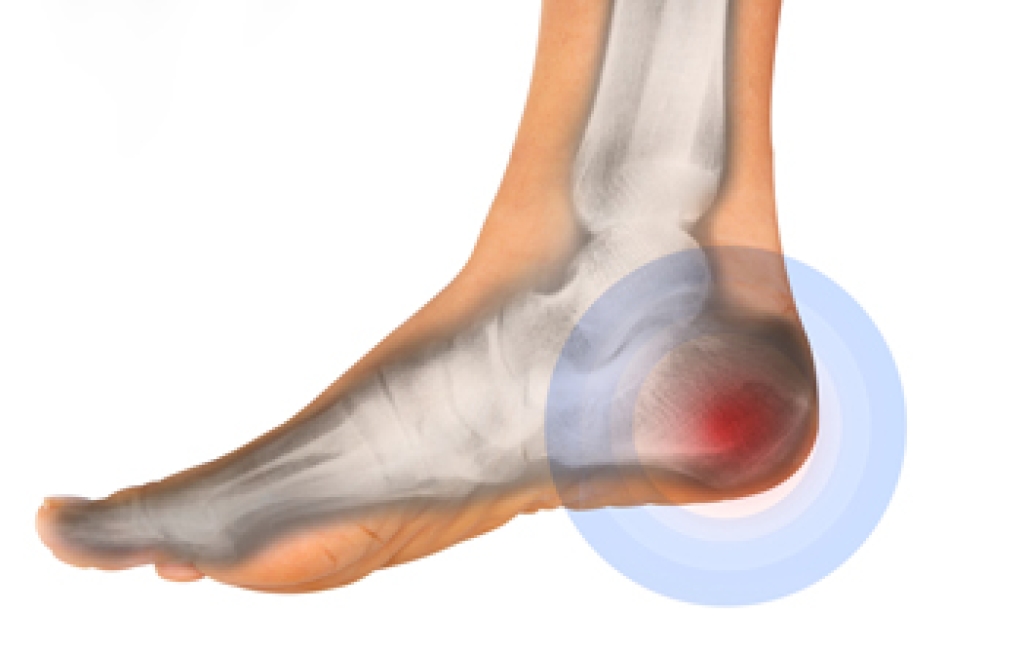

To increase performance and avoid the risk of injury, it is important to choose the right running shoe based on your foot type. The general design of running shoes revolves around pronation, which is how the ankle rolls from outside to inside when the foot strikes the ground.

- Runners who overpronate, or experience an over-abundance of ankle rolling, should choose shoes that provide extra motion control and stability.

- Runners who underpronate, or supinate, have feet that have high arches and lack flexibility, preventing shock absorption. They require shoes with more flexibility and cushion.